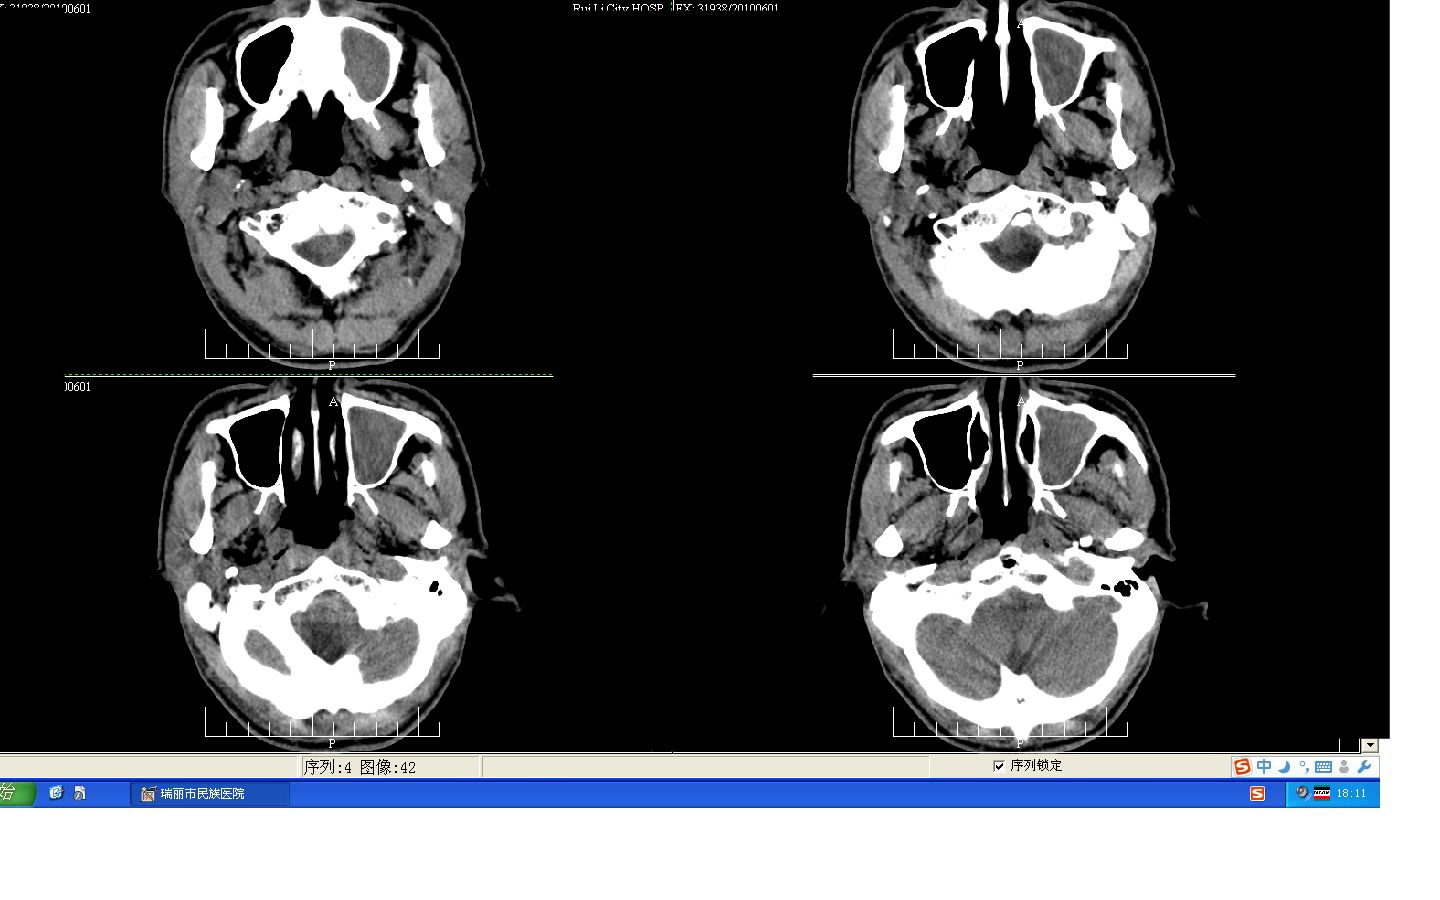

标题: CT26806:女,30岁,左侧面部疼痛10天,请会诊 [打印本页]

标题: CT26806:女,30岁,左侧面部疼痛10天,请会诊

我考虑霉菌性上颌窦、筛窦炎

左侧上颌窦及左侧筛窦炎症。

左侧上颌窦及左侧筛窦炎症。窦口扩大

左侧上颌窦内侧骨壁不完整,窦腔内可见软组织密度填充,内可见更低密度坏死区。不除外恶性,建议活检